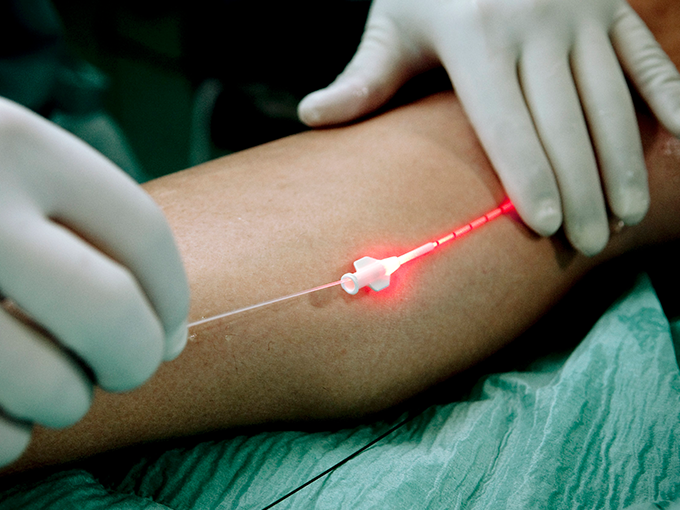

정맥 혈관 내에 레이저 도관을 삽입 후 레이저 광선으로

정맥의 내막을 태워 정맥을 수축시키는 시술법입니다.